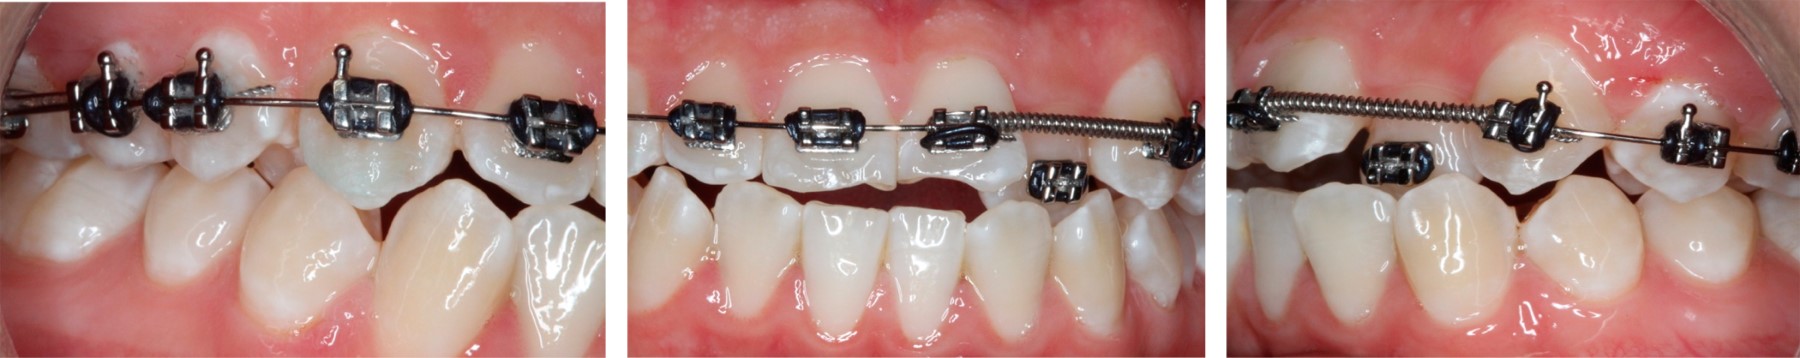

Una vez terminada la alineación y nivelación en ambas arcadas fue necesario tomar una radiografía panorámica y modelos de control para evaluar el paralelismo radicular. Después de recolocar los brackets se reniveló con arcos rectangulares 0.017" × 0.025" de nitinol. Posteriormente, se colocaron arcos de acero inoxidable 0.017" × 0.025" y se terminó asentando la mordida con elásticos clase III de 5/16" con una fuerza de 4.5 oz en conjunto con elásticos triangulares 3/16" 6 oz en los segmentos anteriores (Figura 6).

Figura 6